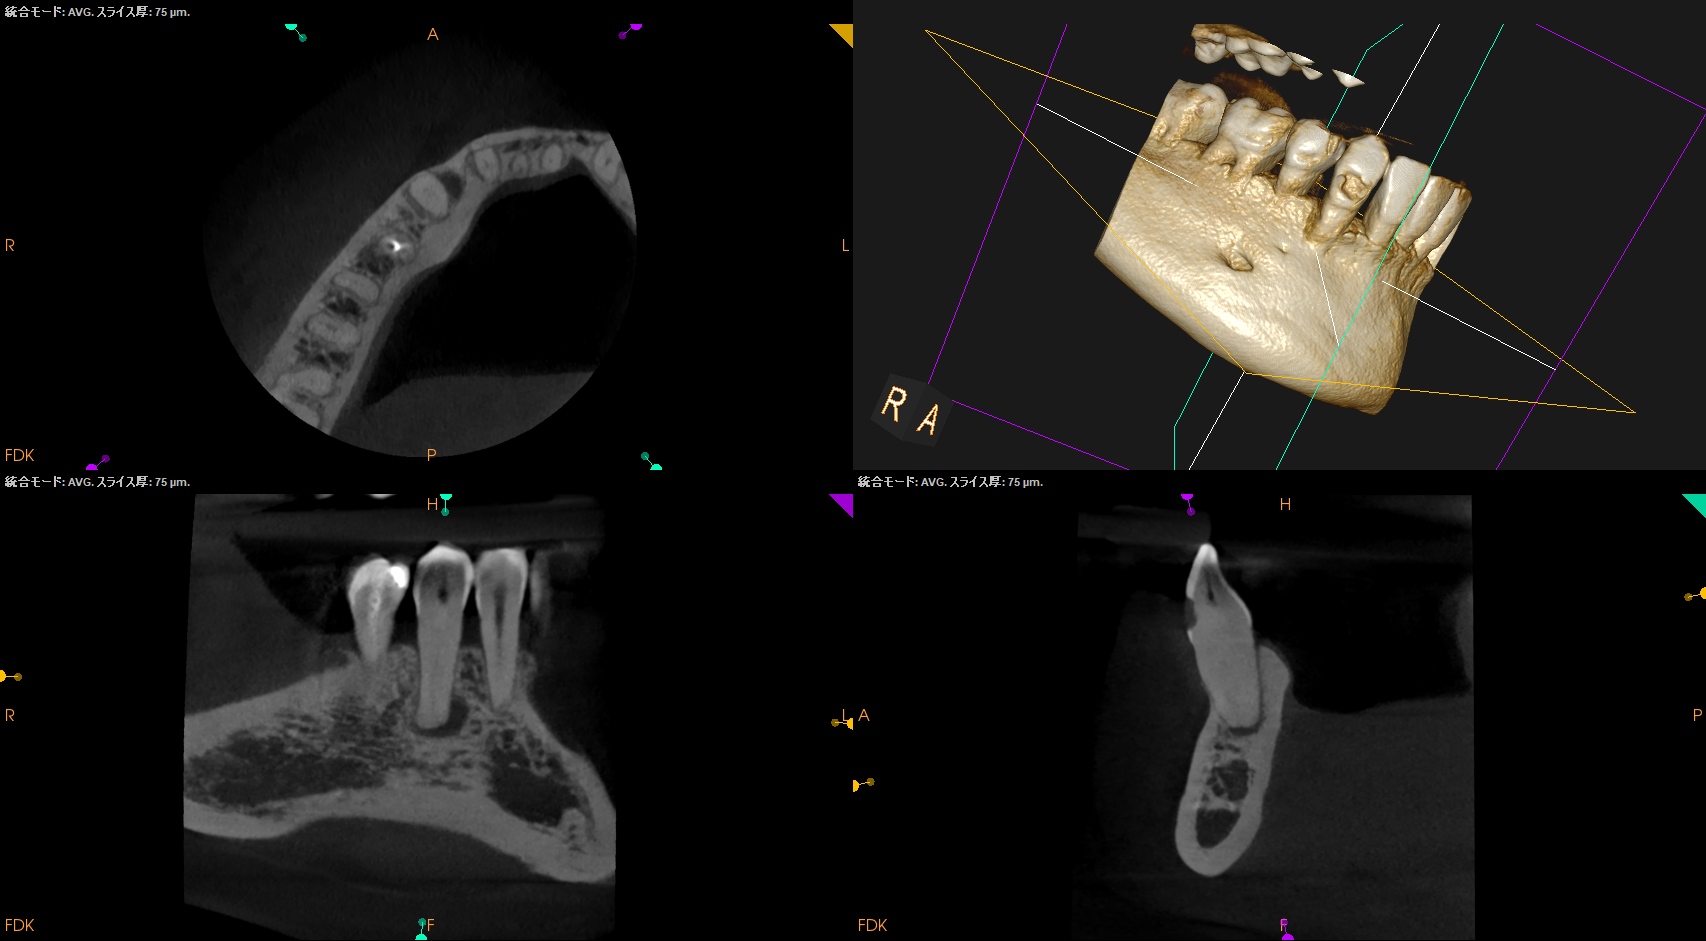

根管治療だがCBCTによれば、

切端からApexまで約25mmだ。

切端を削れば露髄するはず?である。

が、根管は硬かった…。。。

ということで窩洞をレジンで充填し、Intentional Replantationへ移行した。

#27 Intentional Replantation(2026.2.9)

犬歯の抜歯は根尖病変があるものの脱臼作業なしでは成り立たないだろう、ということがこのケースからもわかる。

この後、抜歯窩を精査し口腔外作業へ移行する。

破折はない。

根尖部を3mm切断した。

逆根管形成・逆根管充填した。

PAを撮影した。

問題はないだろう。

抜歯窩を生食で洗浄し、再植した。

術後にPA, CBCTを撮影した。